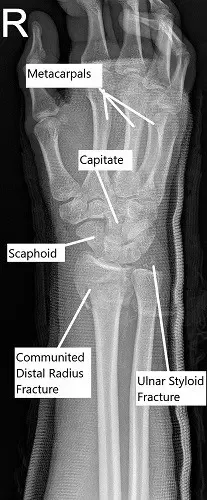

X-ray of the wrist in oblique view showing a comminuted fracture of the distal radius.

On physical examination, there was swelling and tenderness at the right wrist. The distal neurovascular examination of the right hand was normal. X-ray and CT scan of the right wrist revealed a comminuted fracture of the right distal radius, fracture of the ulnar styloid, and disruption of the distal radio-ulnar joint (DRUJ). She had a prior closed reduction at the urgent care which was not adequate.